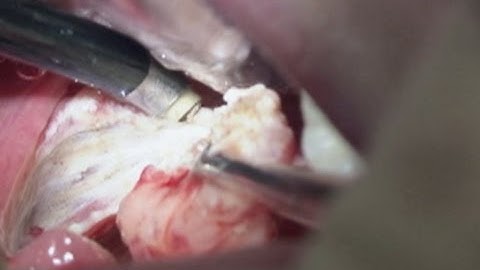

Tonsillectomy Types | Hot Tonsillectomy | Interval Tonsillectomy